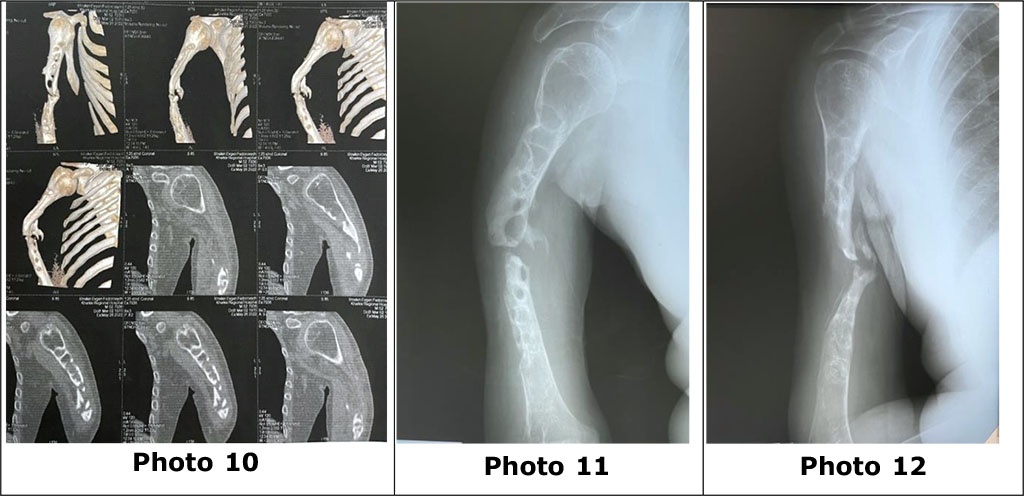

Patient S., a 51-year-old man, sought treatment for non-union after a fracture in the middle third of the humerus after a series of unsuccessful surgical interventions (MOS plate of the right humerus) with the development of significant deformation, sclerosis and osteolytic defects along the proximal and distal fragments of the right humerus bones (photos 10, 11, 12).

Photo 10 - computer tomography, photos 11, 12 - radiographs of the right humerus with signs of the formation of a false joint in the middle third of the humerus, pronounced sclerosis and pathological osteolytic cavities of the proximal and distal parts of the right humerus.